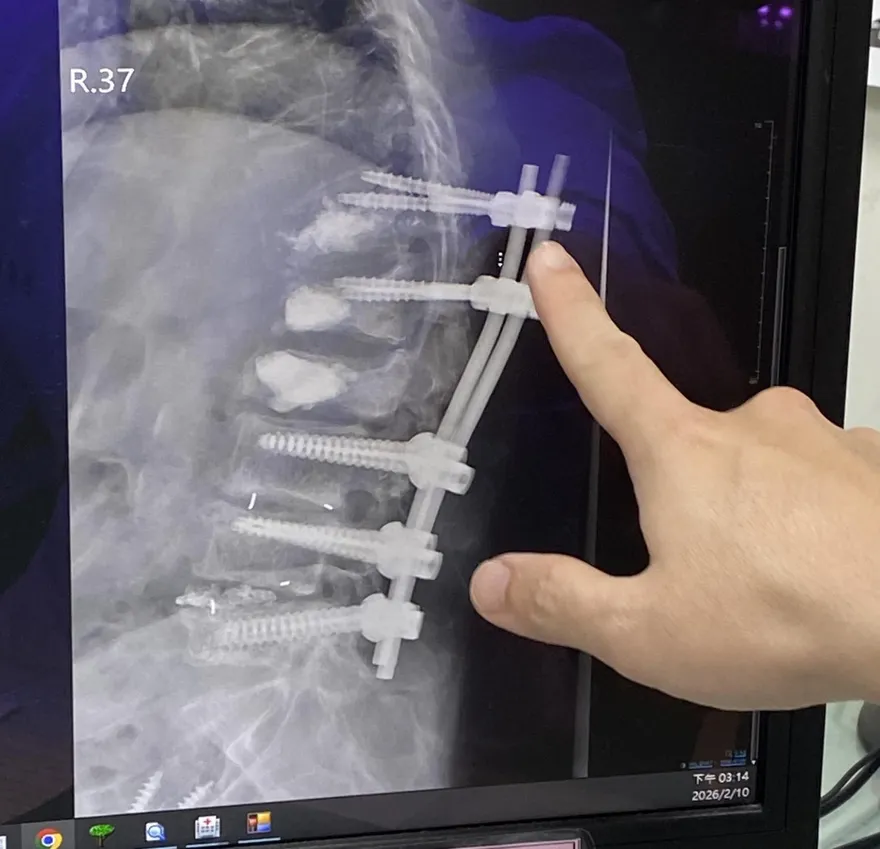

開5刀「灌骨水泥」還是痛!68歲婦靠中醫針灸重新走路

嬤「脊椎連環骨折」體脂43%!骨鬆又肌少症跌倒風險飆